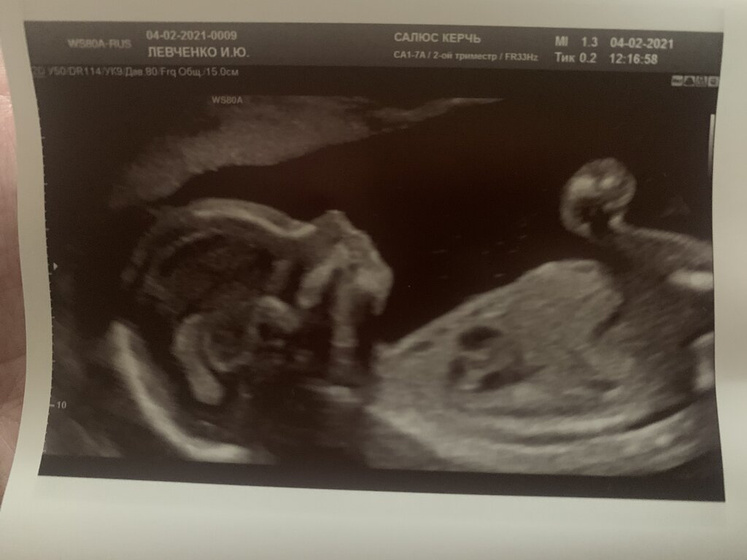

Еженедельные узи… Это конечно клёво, так часто видеть мою кроху, но сама причина пока что не радует. В прошлый раз отслойка была 62мм на 58, толщина 10мм стала 49 на 77 с той же толщиной. В прошлый раз был выраженный гипертонус передней стенки, а теперь умеренный гипертонус перешейка. Плюс ко всему — низкая плацентация. ??? Я ж не ношусь, тяжести не поднимаю, лежу постоянно, если хожу — как улитка. Пью и ставлю все возможное: папаверин, ношпа, магний, транексам, утрожестан три раза в день по 200 и витамины. Бесит уже это все, чесное слово ??♀️